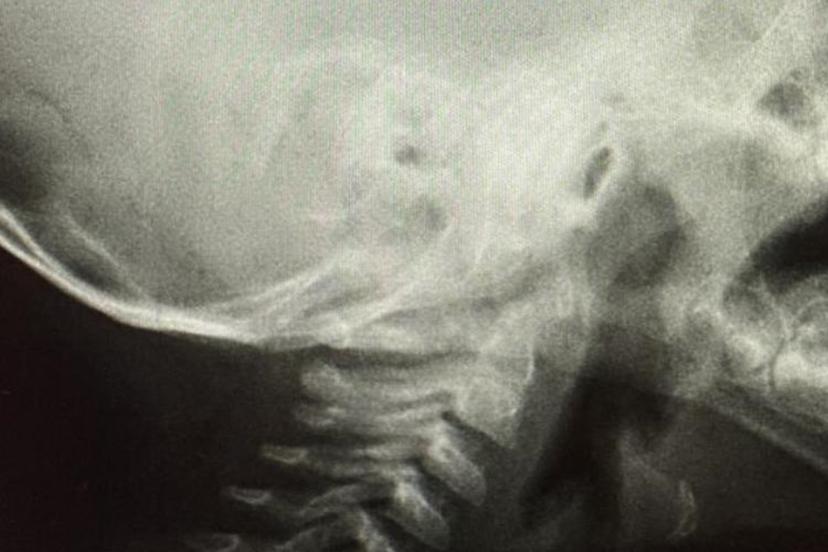

"Kimyasal maddelerin içilmesi de çocuklarda sık görülen ve ciddi sonuçlara yol açabilen bir durumdur. Özellikle yağ çözücü, lavabo açıcı gibi kimyasal maddeler çocuklar tarafından içilebilmekte ve ciddi yemek borusu yanıklarına neden olabilmektedir. Bilinenin aksine bu gibi durumlarda çocuk kesinlikle kusturulmamalıdır. Kusturma, yemek borusunda ikinci kez yanığa yol açabilmektedir. Böyle bir durumda çocuğa herhangi bir yiyecek ya da içecek verilmeden derhal sağlık kuruluşuna başvurulmalıdır. Evlerde kimyasal maddelerin plastik su şişelerine konulması, çocukların bu maddeleri içmesini kolaylaştırmaktadır. Bu tür durumlar ciddi yemek borusu ve damar yanıklarına neden olabilmektedir. Bu nedenle kimyasal maddelerin çocukların ulaşamayacağı, kilitli dolaplarda muhafaza edilmesi gerekmektedir."

Solunum yollarına yabancı cisim kaçmasının da önemli bir risk olduğuna dikkat çeken Özkaya "Solunum yollarına yabancı cisim kaçması da günlük hayatta sık karşılaşılan ve hayati tehlike oluşturabilen durumlardan biridir. Özellikle üç yaşına kadar olan çocuklara çerez, fındık, fıstık, çekirdek gibi sert gıdaların verilmemesi gerekmektedir. Bu gıdalar solunum yollarına kaçarak ciddi nefes darlığına neden olabilmektedir. Böyle bir durumla karşılaşıldığında, mümkünse Heimlich manevrası uygulanmalı ve 112 Acil Servis eşliğinde en yakın sağlık kuruluşuna başvurulmalıdır. Bu tür vakaların operasyon gerektirebileceğine dikkat çekilerek, özellikle yemek borusunda kalan disk pillerin son derece tehlikeli olduğu vurgulanmaktadır. Disk piller, çocukta belirgin bir şikâyet olmasa bile kısa sürede yemek borusunda yanıklara ve delinmelere yol açabilmekte, hayati risk oluşturabilmektedir. Bu nedenle acil olarak ameliyathane ortamında çıkarılmaları gerekmektedir." şeklinde konuştu.